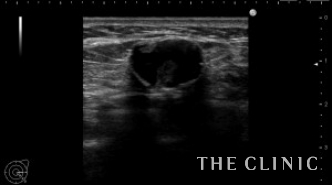

左乳腺下にオイルシストが2個ありました。

エコー下に穿刺吸引しました。

白濁したオイルが引けました。この後、コンデンスリッチ豊胸を行いました。